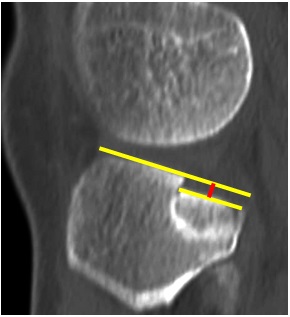

Mediante la observación de los diferentes cortes tomográficos hallamos dos variantes de depresión (TP) de la superficie articular: tipo A, (hundimiento) donde hay un hundimiento circunscripto del platillo en 18 pacientes (66 % en nuestros casos) (Fig. 4), y tipo B, (declinación) impactación del hueso esponjoso con una inclinación hacia posterior del relieve articular en 15 pacientes (Fig. 5).

Figura 4. Hundimiento. La depresión pura de la superficie articular se limita al cuadrante posterolateral del platillo tibial.